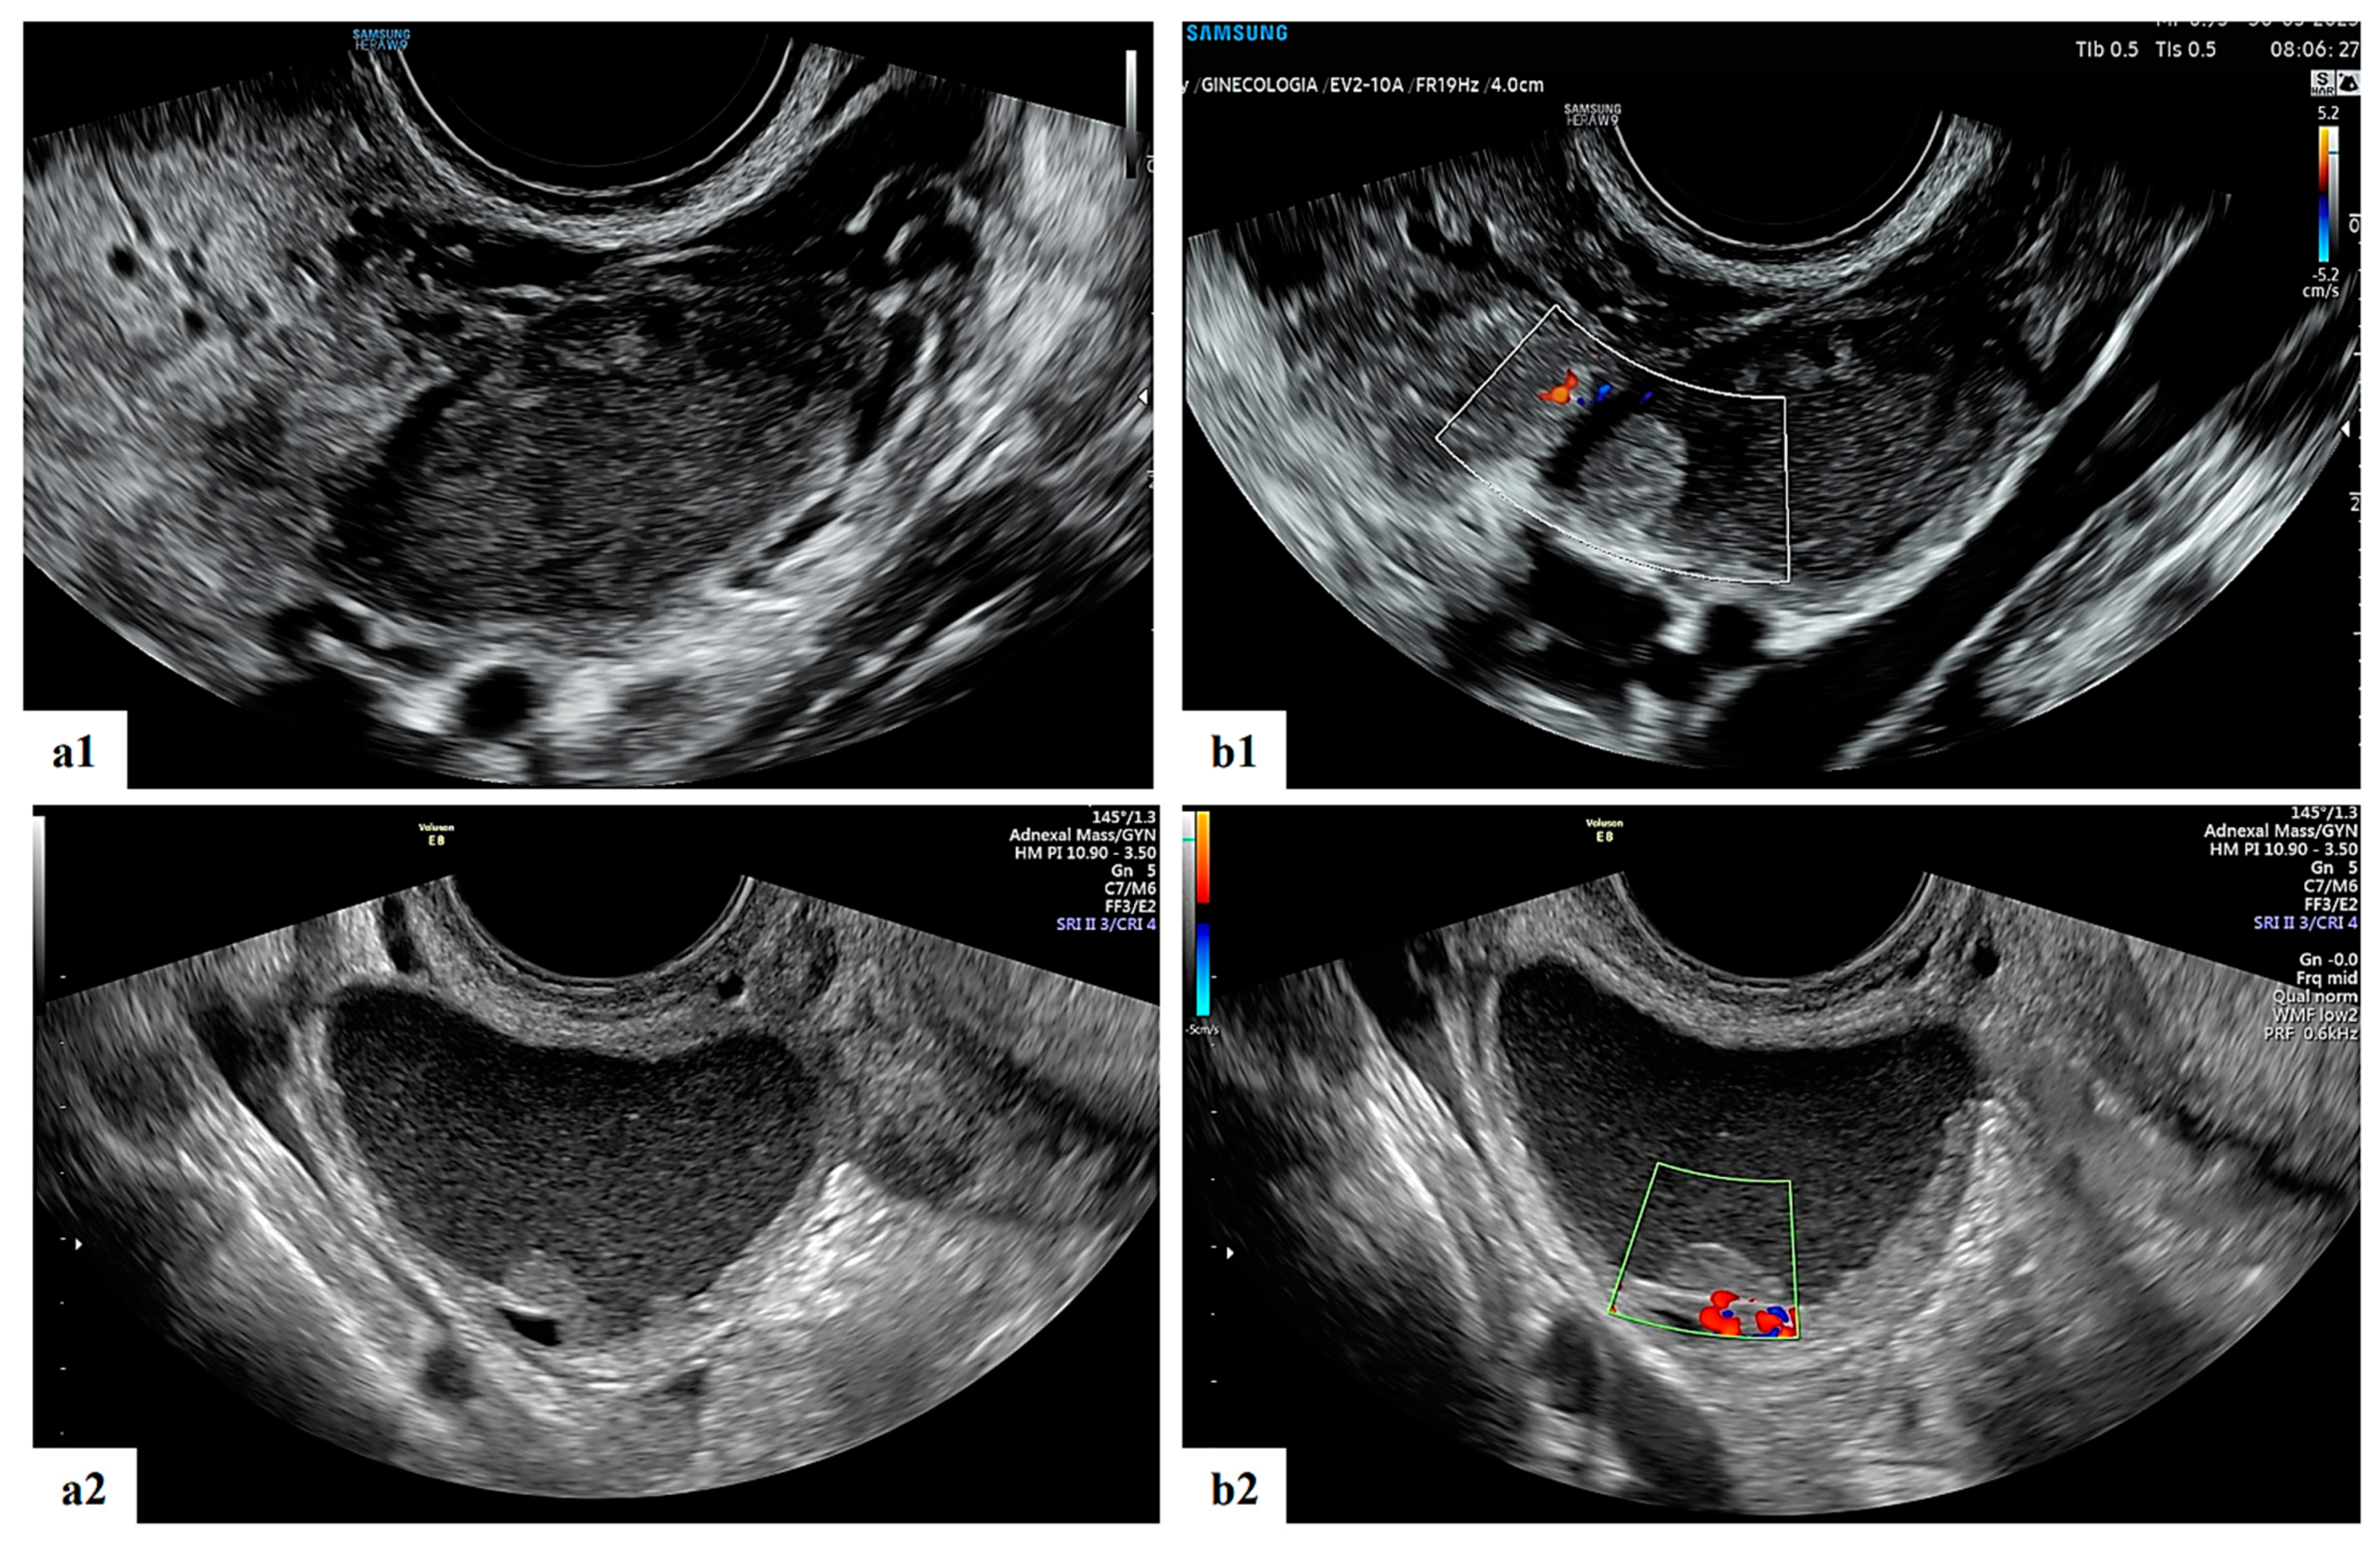

- Mascilini, F.; Moruzzi, C.; Giansiracusa, C.; Guastafierro, F.; Savelli, L.; De Meis, L.; Epstein, E.; Timor-Tritsch, I.E.; Mailath-Pokorny, M.; Ercoli, A.; et al. Imaging in gynecological disease. 10: Clinical and ultrasound characteristics of decidualized endometriomas surgically removed during pregnancy. Ultrasound Obstet. Gynecol. 2014, 44, 354–360. [Google Scholar] [CrossRef]

- Moro, F.; Mascilini, F.; Pasciuto, T.; Leombroni, M.; Li Destri, M.; De Blasis, I.; Garofalo, S.; Scambia, G.; Testa, A.C. Ultrasound features and clinical outcome of patients with malignant ovarian masses diagnosed during pregnancy: Experience of a gynecological oncology ultrasound center. Int. J. Gynecol. Cancer 2019, 29, 1182–1194. [Google Scholar] [CrossRef]

| Papillation flow Present Absent | 2/4 2/4 |